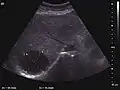

Liver cyst

Hydatid liver cyst. Diagnostic criteria are the presence of membranes and sediment inside.